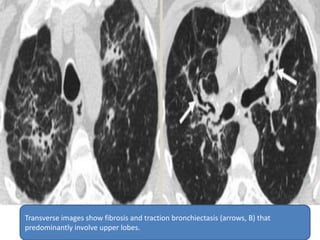

 Parenchymal involvement by sarcoidosis can

lead to upper and mid lung fibrosis and

traction bronchiectasis, typically associated

with multiple nodules in a perilymphatic

distribution. Mediastinal and bilateral

symmetric lymphadenopathy is common,

although it can regress as the interstitial disease

worsens.

Transverse images show fibrosis and traction bronchiectasis (arrows, B) that

predominantly involve upper lobes.